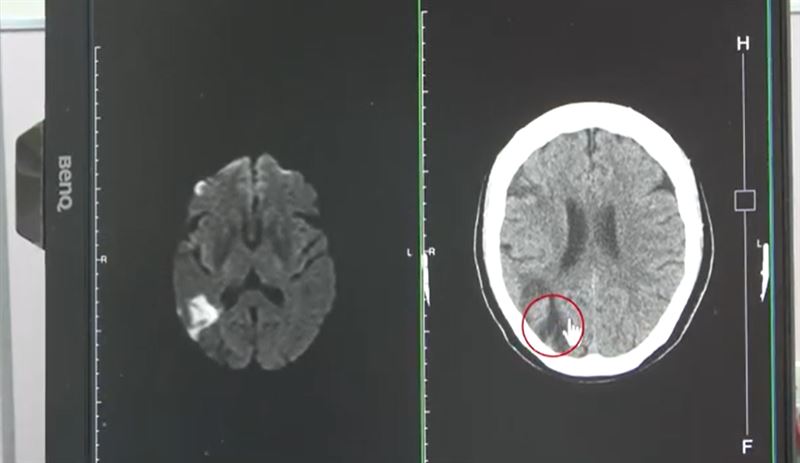

張峻誠醫師表示,聽完患者描述,研判症狀即為中風,先安排電腦斷層檢查,果然看到右邊中大腦動脈阻塞,為了確認阻塞範圍,進一步做核磁共振,詳細判讀後發現,婦人當時眼睛出現模糊時已經初次中風,只是比較幸運範圍較小,沒有出現手腳無力、無法行走的情形。

從檢查報告中發現,患者有三高問題,尤其膽固醇嚴重超標,平時沒有控制,第一次中風時出現視力模糊,為非典型症狀,沒有警覺是中風症狀,才導致阻塞症狀加劇,幸運的是,阻塞範圍沒有擴大,否則恐怕會造成半身癱瘓。